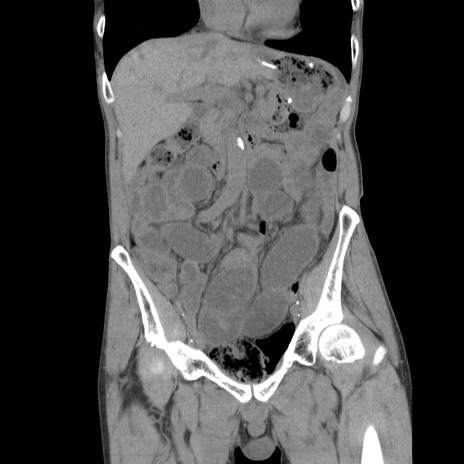

症例11(冠状断像)

【症例】 60歳代男性

【主訴】 下腹部痛

【現病歴】 本日夜中より下腹部痛の症状認め、受診。

【既往歴】 膀胱癌(膀胱全摘+尿管皮膚瘻術) 、胃癌術後

【身体所見】 BT 35.3℃、PR 58/min、BP 136/98mHg、腹部平坦、軟、腸蠕動音±、ストマ留置あり、左上腹部~正中部に圧痛あり、反跳痛なし。

【データ】WBC 5100、CRP0.01